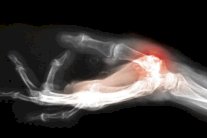

إيلاف: خلصت دراسة حديثة أجراها باحثون في جامعة هارفارد الأميركية إلى أن التهاب المفاصل في الركبتين هو مرض يمكن الوقاية منه.

ويقول الباحثون إن هذا المرض أصبح يصيب الكثير من الناس بسبب انتشار السمنة والتغيرات في نمط الحياة مثل النظام الغذائي وأنواع الأحذية المنتشرة في الأسواق، وأضافوا: "مرض هشاشة العظام يؤثر في 8.8 ملايين شخص في بريطانيا الذين تزيد أعمارهم عن 45 سنة".

وقال دانيال ليبرمان، أستاذ العلوم البيولوجية في جامعة هارفارد، إنه يمكن تجنب العديد من حالات الإصابة بالتهاب المفاصل بخطوات بسيطة، مضيفا: «التهاب المفاصل في الركبة ليس نتيجة ضرورية للشيخوخة»، وقدم ليبرمان مجموعة من النصائح للوقاية من هذا المرض: